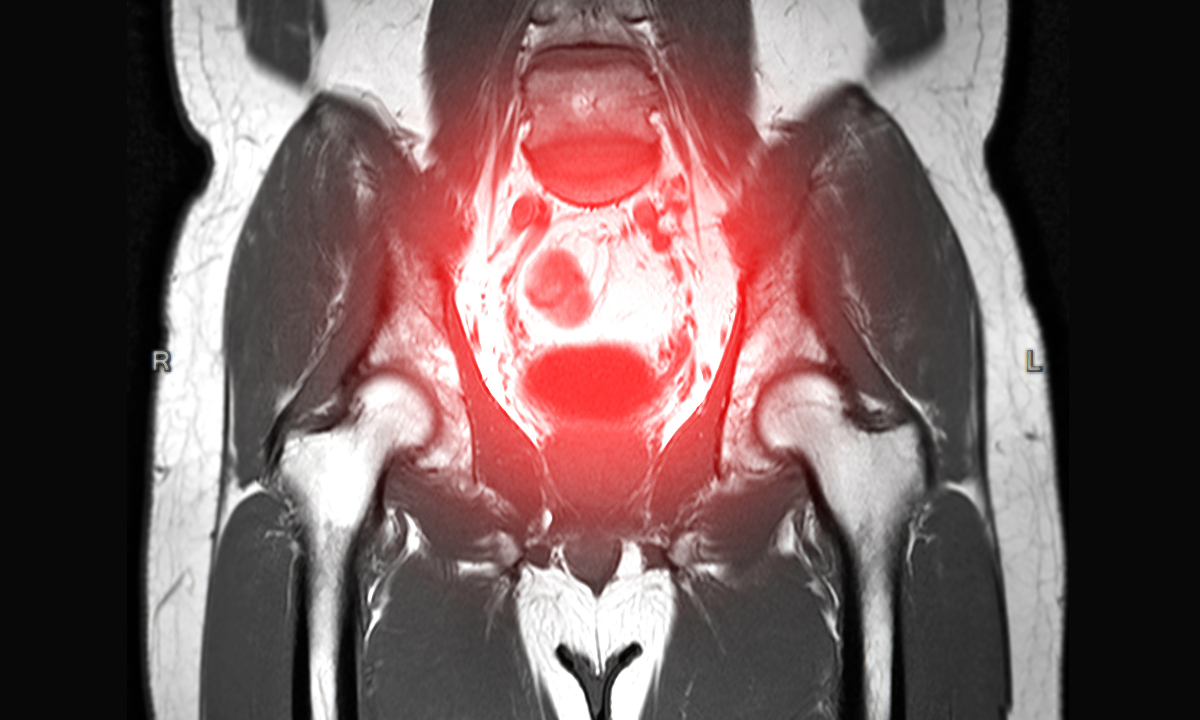

MRI uses strong magnets and radio waves to create highly detailed images of the pelvic area. This helps your doctor see soft tissues clearly and identify whether an ovarian mass is likely benign or cancerous. MRI is especially good at distinguishing between dermoid cysts, endometriotic cysts, and fibroids, which can sometimes appear suspicious on ultrasound.

MRI offers more detailed information than an ultrasound. It produces clear images that help doctors assess the nature of an ovarian mass and see if the cancer has spread beyond the ovaries.

Distinguishing benign from cancerous masses

One of MRI’s key strengths is helping doctors tell the difference between harmless (benign) and cancerous ovarian masses. It produces highly detailed images that allows your radiologist to spot subtle differences between conditions such as ovarian cysts, ovarian cancer, and other similar growths.

The scan shows details about the tissue structure and whether the mass is solid or fluid-filled. For instance, functional cysts typically appear as fluid-filled areas with little to no solid tissue. These distinctions help your doctor decide whether surgery or simple monitoring is the best approach.

Detecting cancer spread and staging

If cancer is present, MRI plays an important role in showing how far it has spread. It’s currently one of the most accurate imaging tools for evaluating cancer spread in the abdomen, which is crucial for treatment planning.